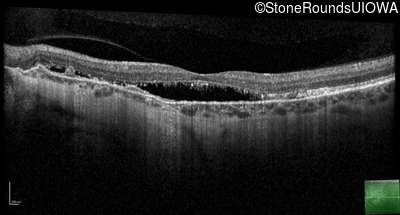

Age at visit: 58 years